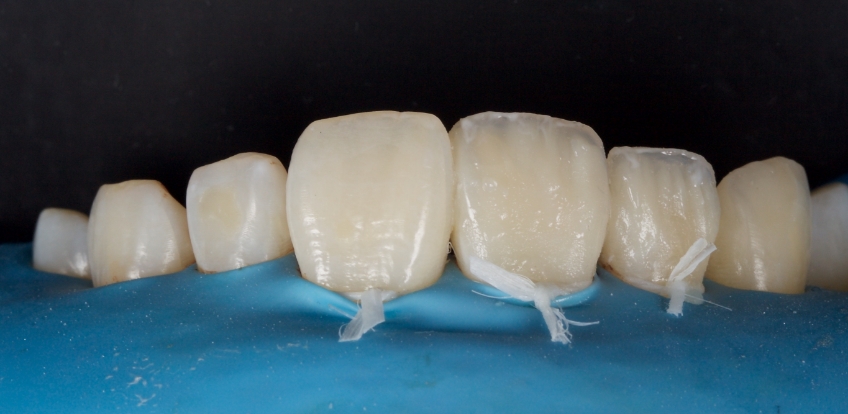

Any biofilm and aprismatic enamel were removed from the tooth, and the fragment was fragmented with light hydro abrasion with 29-micron alumina at 2-3 bar pressure. The tooth and the fragment were etched with 37% phosphoric acid (Ultradent), and a fourth-generation dentin bonding agent (Kerr, OptiBond FL) was applied (the adhesive component was not light-cured).

The fragment was luted to the tooth with heated chromatic enamel shade composite (GC G-aenial A2 shade). The heater used was a Calset Warmer from Addent. The excess composite was cleaned with an interproximal carver from American Eagle and smoothed with a number three brush and modeling resin (Brush & Sculpt from Cosmedent).

The composite was heated because it gained lower viscosity to improve adaptation. Plus, heating increases the conversion of monomer to polymer, which improves the physical characteristics of the resin, such as flexural strength and wear resistance, according to research by Da Costa, Hilton, and Swift in 2011.

The resin was polymerized, and the oxygen-inhibited layer was removed by polymerization under glycerine.

The enamel fracture on 2.1 was untouched and will be managed in conjunction with esthetic management of the white hypo calcification at a later time.